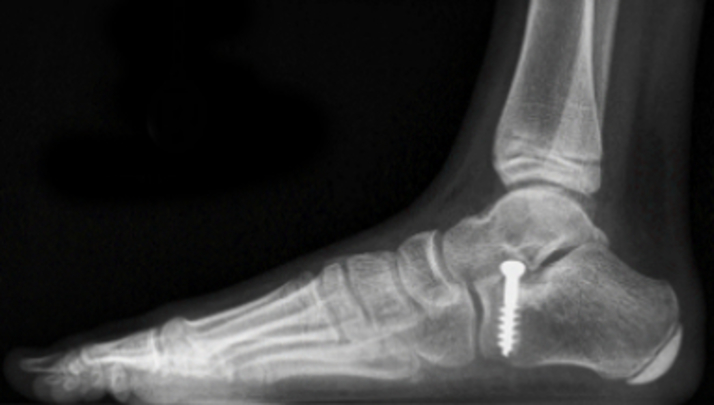

Wieder eine OP, wieder am Fuß- nun aber bei Julius